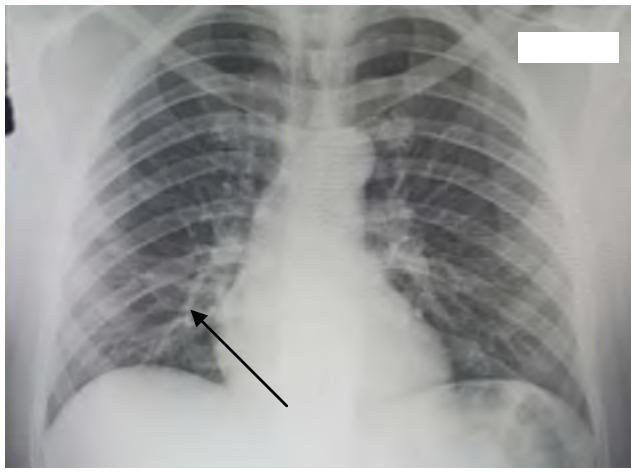

Chest X-ray showed a small basal alveolar image on the right, consistent with gastric aspiration. (Figure 2)

Figure 2: Right basal Image on Chest X-Ray